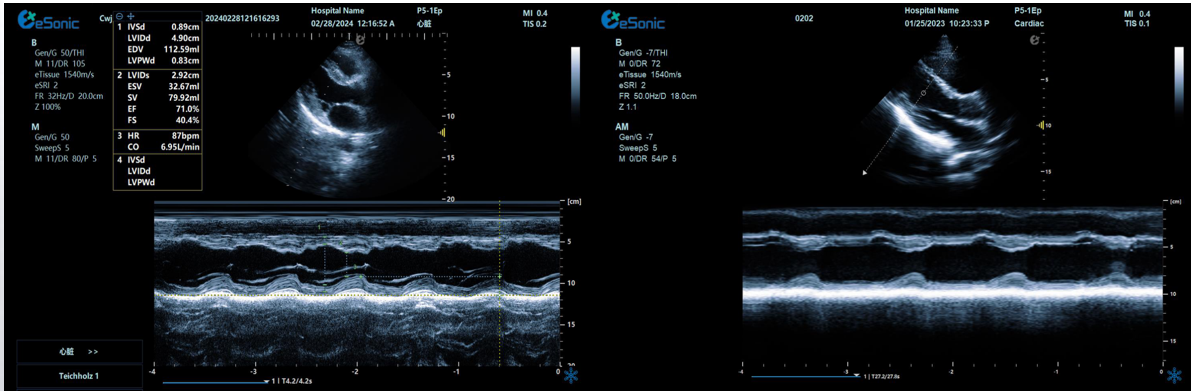

相关心脏应用功能--M型、解剖M型

18dd0675d53918b7d05ea7a823af71a.png

M型-最常用的心功能检测法;高血压病除二维观察外,其室壁增厚及心腔大小的改变,均也可通过M型测量而获得

解剖M型-适用于心尖上翘者、瘦长体形者、室壁瘤形成等...

相关心脏应用功能--M型、解剖M型技术总结:

1edf4ffc259114ab6502340e160add1.pngM型超声是评估心脏功能的重要方法之一,通过其高速的取样帧频,可以将心脏各个阶段的运动状态显示出来。

解剖m型:

不受角度限制,打破技术壁垒不影响M型图谱分辨率。

三线解剖M型:

同一心动周期,多节段评估心功能。

解决节段运动异常和判断同步化运动。

彩色M型:

直观显示室璧运动和血流动力学关系。

更精准判断血流时向,更精准评估心脏功能。